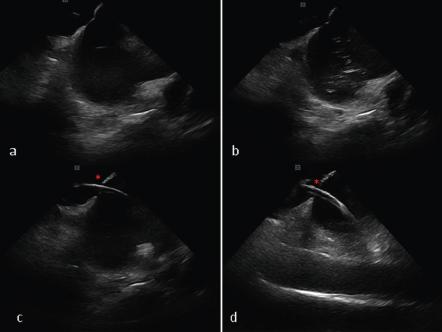

Figure 2